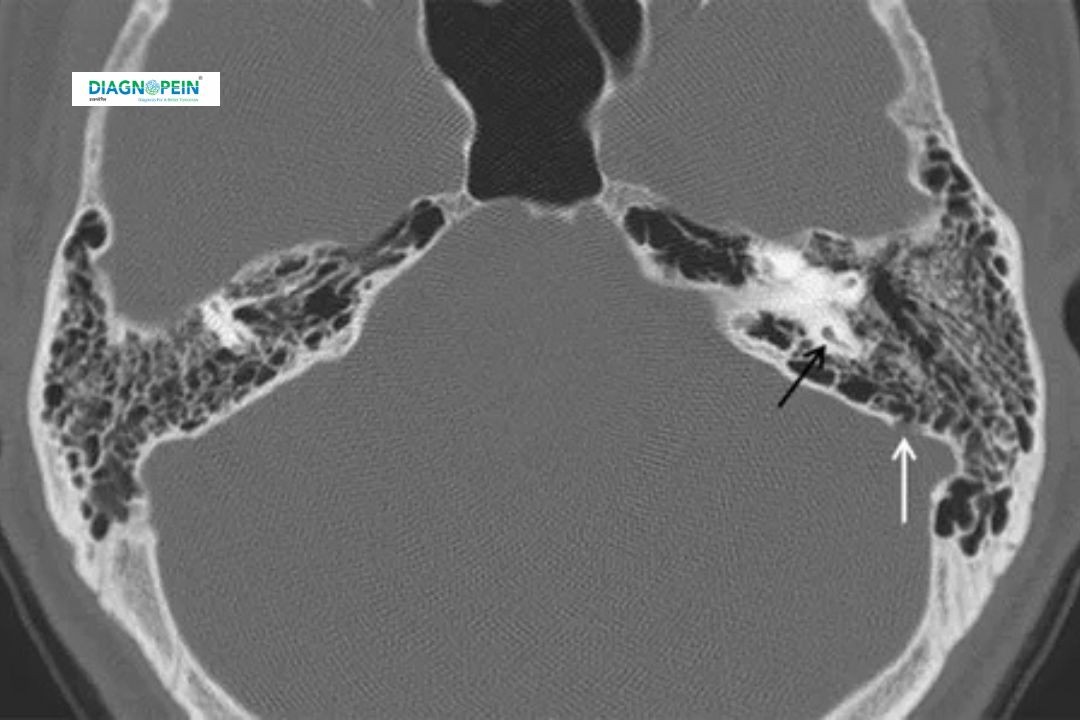

The MASTOID B/L VIEW test is crucial for diagnosing various ear and skull-related conditions, especially those associated with chronic ear infections or trauma. This view offers detailed visualization of both mastoid processes, helping clinicians detect abnormalities in the bony structure, air sinuses, or evidence of mastoiditis (inflammation of mastoid air cells).

The MASTOID B/L View X-ray focuses on:

1. Evaluation of mastoid air cells.

2. Assessment of temporal bone integrity.

3. Detection of fluid levels, sclerosis, or erosions indicating infection.

4. Comparison of left and right mastoid structures for abnormalities.